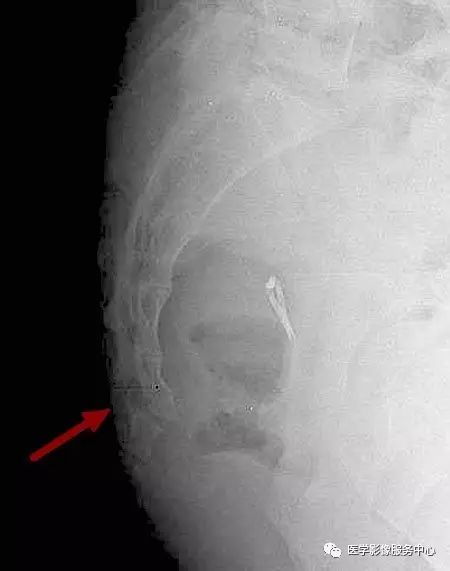

附病例(X线+CT):

病人女性,外伤后骶尾部疼痛,dr片示骶尾关节对应关系差,骶5椎体欠规则。ct重建示骶5椎体粉碎性骨折!

X线:

CT: